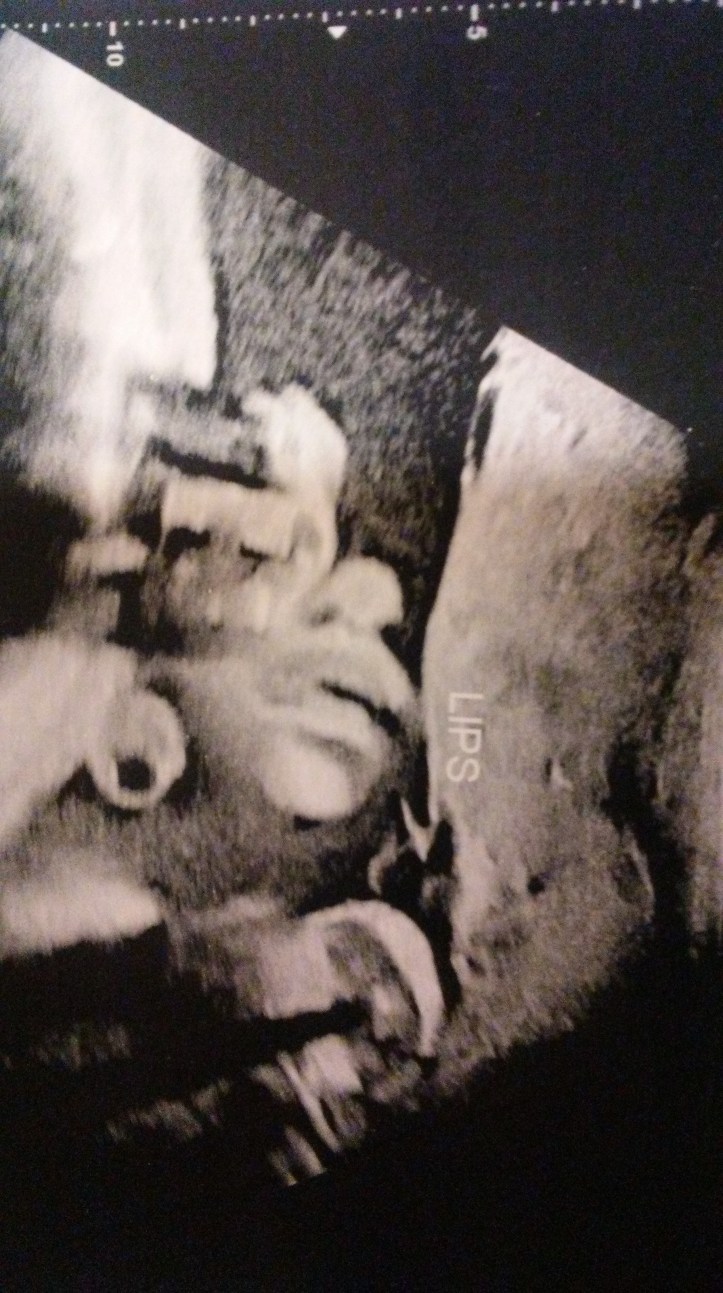

I have a job interview tomorrow to go back into caregiving. I don’t necessarily have to work but the tight budget thing is gets old and I have big plans for this lovely house and yard and y’all know that takes a little cash. So, all good things ahead. Blog posts about redecorating, renovating the kitchen, landscaping the gardens, recipes, and a simple life are still to come. And my new grandbaby will be here soon. I am relieved, overwhelmed, inspired, and grateful. Thanks for following along on the ride. This is indeed a very good life.